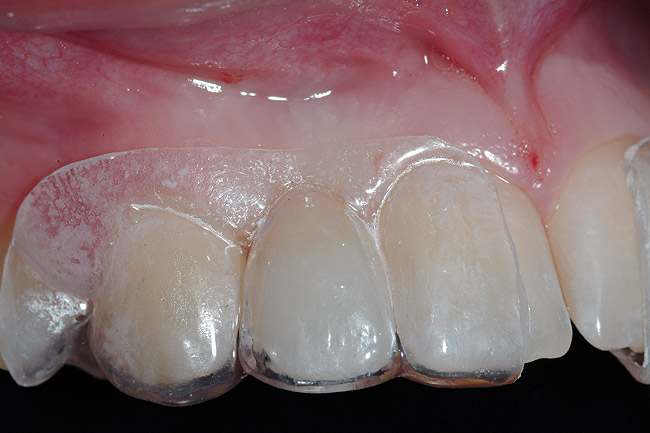

A 19-year-old non-smoking female presented for tooth replacement at the maxillary right and left lateral incisors, which were congenitally missing (Figure 1). The post-orthodontic result was adequate for the placement of 3-mm one-piece small-diameter implants. The preoperative radiographs can be seen in Figure 2 and Figure 3. The pretreatment clinical view in Figure 4 and Figure 5 shows the small intertooth space present in the lateral incisor areas. One of the most challenging tasks with congenitally missing lateral incisor cases is to create an acceptable soft tissue emergence profile from a crestal profile that is flat from the mesial of the canines to the distal of the centrals (Figure 4 and Figure 5). After pretreatment planning which consisted of a complete medical and dental history, radiographic analysis, and upper and lower study models mounted by a facebow transfer technique, the fabrication of a TempStent II surgical guide was completed. Figure 6 and Figure 7 show the occlusal view of the TempStent II guide on the study cast and in the oral cavity, respectively.

Figure 6  Occlusal view, TempStent II Surgical Guide.

Figure 6

Figure 7  Intraoral occlusal view, TempStent II Surgical Guide.

Figure 7